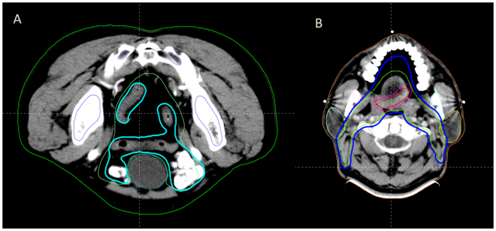

CT/MRI配准图像

并成功实现了复杂靶区的自动勾画,以鼻咽癌靶区勾画为例,传统手工勾画需要2-3小时,而自动勾画只需2分钟,大大简化了放射治疗的靶区勾画流程,从而缩短了患者的住院周期。

腹部和头颈肿瘤自动勾画效果